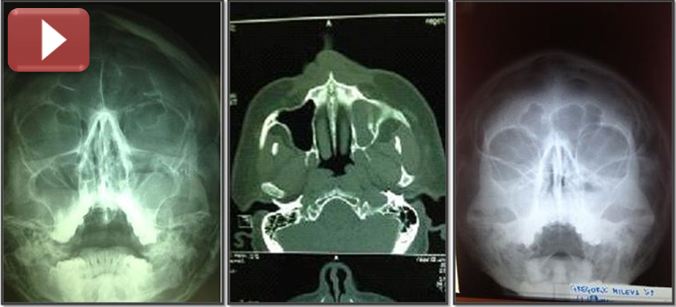

| Upala ovih sinusa može biti akutna (traje kraće od 3 nedelje), subakutna (proces je još uvek reverzibilan), hronična (traje od 3-8 nedelja, godinama) i recidivirajuća- karakteriše je nekoliko akutnih napada u toku godine. Uzroci su virusi, bakterije i gljivice. Afekciiji doprinose alergijska oboljenja sluznice nosa, nazalna opstrukcija (devijacija nosne pregrade, polipi, uvećane nosne školjke, i dr.).Kod oko 40% upala maksilarnih sinusa proces zahvata i prednje etmoidalne ćelije. Na dentogene infekcije sinusa otpada oko 10% (apikalni procesi na korenu zuba) kada se upala može manifestovati kao primarni hronični sinusitis, koji nakon egzacerbacije prelazi u sekundarni akutni sinusitis. Ako se radi o rinogenoj infekciji proces je obično obostran, a kod dentogenih jednostran. Kliničkim pregledom nalazimo prisustvo mukopurulentnog , seromukoznog, sangvilentnog sekreta u srednjem i donjem nosnom hodniku, uz simptome kao što su: nazalna opstrukcija,postnazalni drip,zadah iz usta,oslabljeno čulo mirisa,subfebrilne temperature,glavobolje,lokalna bol,hronični faringitis,produktivni kašalj ,lak otok donjih očnih kapaka,bledilo,apatija, itd.Takodje, pregledom ždrela i epifarinksa se vidi slivanje sekreta niz stražnji zid ždrela. Rtg snimkom PNS najčešće nalazimo difuzno zasenčenje čitavog maksilarnog sinusa ili nivo koji je odlika patološkog sekreta u njemu. EHO sinusa ne treba izostaviti kao dijagnostičku proceduru, posebno kod dece. Kvalitetniji pregled stanja u sinusima nam pruža CT ili NMR, ili pregled kamerom (nazalna endoskopija) kojom inspiciramo „predsoblje“ sinusa preko koga sinusi komuniciraju sa nosom.Sinusoskopija je zlatni standard u dijagnostici ovog obolenja. Bris nosa,test na inhalatorne alergene,imunoglobuline,Eo u nosu i drugo, nekad je neophodno uraditi radi otkrivanja etiologije bolesti. Nakon postavljanja dijagnoze sprovodi se medikamentozna terapija(antibiotici,mukolitici,kapi za nos,ispiranje nosa,lokalni kortikosteroidi,inhalacije,analgetici i dr.).U slučaju čestih recidivirajućih upala treba se okrenuti hirurškom rešavanju prisutne endonazalne patologije (nosna pregrada,nosne školjke,polipi itd.) koja doprinosi nastanku pomenutog oboljenja. Ako nema uspeha konzervativnim lečenjem ili isto daje slabe rezultate, preporučuju se operativne procedure. |

![]() Na maksilarnim sinusima, kod hroničnog gnojnog procesa ili empijema sinusa, radi se intervencija u vidu punkcija sinusa (dijagnostičko-terapeutska) kroz donji nosni hodnik. Punkcija sinusa je posebno inducirana u slučajevima kada preti opasnost od komplikacija. Oštrom iglom se udje u sinus, aspirira sekret , ispere sinus i ubaci odgovarajući lek (antibiotik,kortikosteroid). Nekada ovu proceduru treba ponoviti više puta u razmaku od 24-48 h. Rezultati su zadovoljavajući. Procedura urađena od strane iskusnog ORL uglavnom je bezbolna, a blagodet se oseti odmah. Komplikacije su retke. Druga procedura je pravljenje većeg otvora ispod donje nosne školjke prema sinusu, veličine oko 0,8-1,0 cm, radi izvlačenja sekreta iz sinusa (polietilenskom cevčicom) ispiranja fiziološkim rastvorom, ubacivanja leka, itd. Intervencija se radi u ambulantnim uslovima i lokalnoj anesteziji. Izuzetno je uspešna u slučajevima gde je pod sinusa ispod poda nosa. Kroz pomenuti otvor se i narednih dana, po potrebi, može vršiti lavacija sinusa. Metoda je poznata u medicini pod imenom „donja meatotomija“, a u narodu kao „čišćenje sinusa“. U daljem nastavku lečenja ordiniraju se antibiotici uz vazokonstriktorne kapi za nos i lokalni kortikosteroidi. Ako se sluznica u predelu koštanog otvora „obradi“ radiotalasima nema krvarenja ni potrebe za tamponadom. Srednja meatotomija se može izvesti tupom iglom ili specijalnom radiotalasnom elektrodom. Proširi se prirodni ostijum kroz koji se drenira maksilarni sinus. Ako je sluznica edematozna, polipozno izmenjena i blokira izvodni kanal sinusa, možemo je reducirati, odstraniti i time proširiti kanal.Prednost dajemo radiofrekvencijskim talasima.. U nekim slučajevima je neophodno uraditi srednju i donju meatotomiju.Navedene intervencije se mogu raditi u lokalnoj anesteziji, pod mikroskopom i u ambulantnim uslovima. Zahtevaju dodatno odgovarajuće konzervativno lečenje. Ponekad iziskuju redukciju donje i srednje nosne školjke. Ostale operacije na maksilarnom sinusu se izvode ,uglavnom, u bolničkim uslovima(FESS,Caldwel –Luck i dr.) |

kliknite na sliku za uvećan prikaz